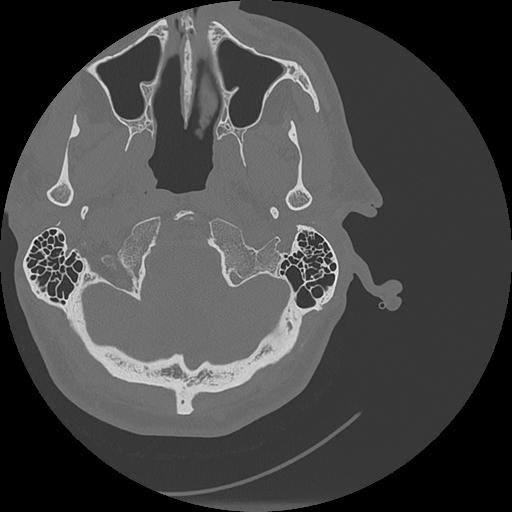

7 HUESO,,Vol,0.5,HUESO,,